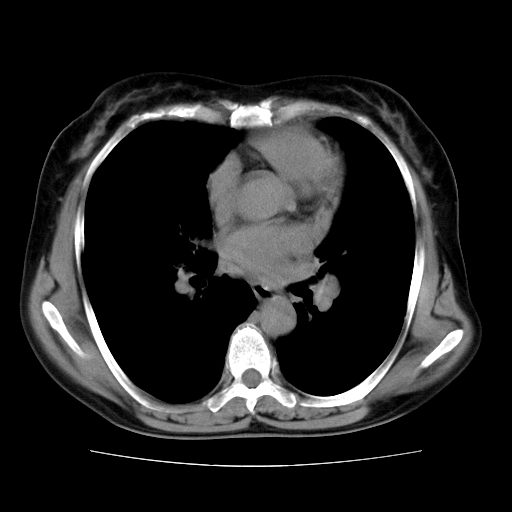

标题: CT10838:女性,56岁,是上腔静脉钙化还是淋巴结钙化?

女性,56岁临床诊断为胃贲门ca,术前检查发现,此钙化灶,对此科内稍有争论!请各位老师看看!是上腔的还是淋巴结的?有意义吗?

胸锁关节层面的是淋巴结钙化,气管前腔静脉后的钙化灶占了4个层面,不知层厚是多少?看样子应该是7--10毫米之间,那么这病灶最小纵径得有28毫米!应该提示点什么了,没传肺窗,估计肺内没有病变?

左锁骨下静脉和头臂静脉会合后形成是上腔静脉,此钙化位于两血管回合的腔静脉后方、气管右前方,这个位置没有其他结构,应该是淋巴结钙化。一般多为淋巴结核后钙化,没有临床意义。